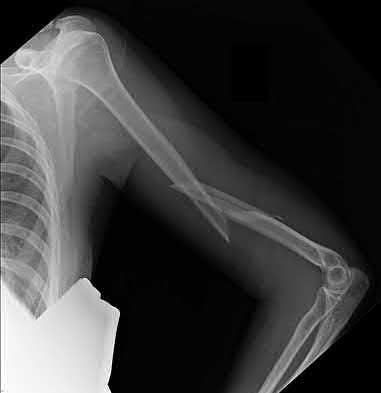

4. # After undergoing the treatment seen in Figure A, when should a patient be expected to safely operate the brakes of an automobile?

1. 6 weeks

2. 2 -4 weeks

3. 6 months

4. 8-9 weeks

5. 3 months

Corrent answer: 4

Figure A shows a patient after an open reduction and internal fixation of a bimalleolar ankle fracture.

Egol et al showed that by nine weeks, the total braking time of patients who had undergone fixation of a displaced right ankle fracture returns to the normal, baseline value.

Egol et al, also found that appropriate braking time returns at a point 6 weeks after initiation of weightbearing after treatment of lower extremity long bone and periarticular fractures, as examined with a driving simulator. No differences were seen in return of braking time between periarticular fractures and long bone injuries.